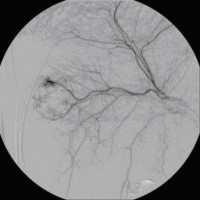

Superselektive transarterielle Chemoembolisation (TACE) mit Sondierung eines tumorversorgenden Gefäßes 2

(Bild 4 von 5)